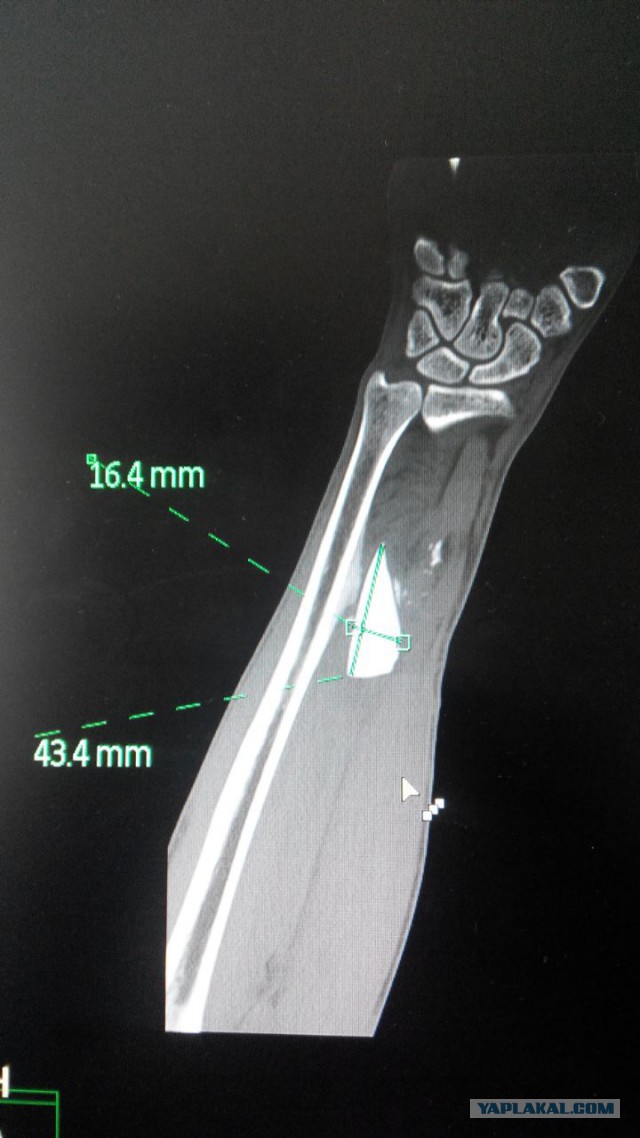

rostomografавтор 22 ноя 2015 в 19:48